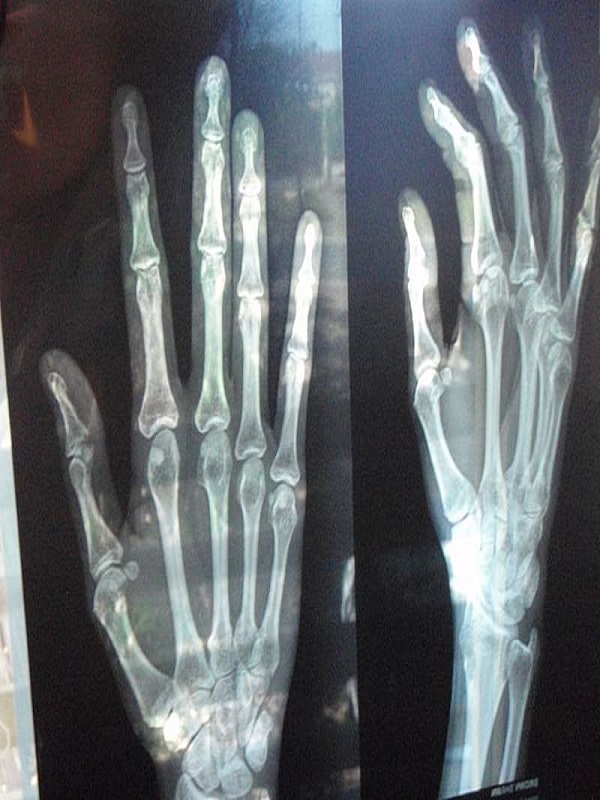

Head Injury

Traumatic brain injury usually results from a violent blow or jolt to the head or body. An object that goes through brain tissue, such as a bullet or shattered piece of skull, also can cause traumatic brain injury.